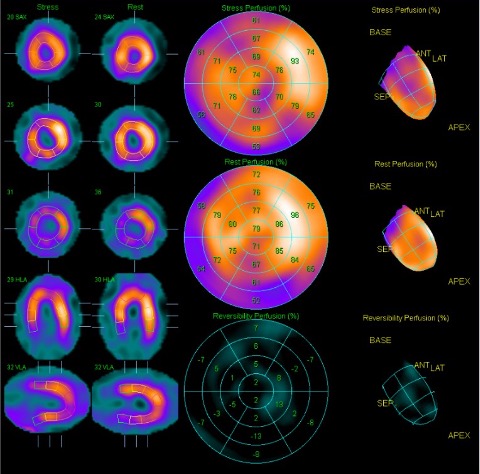

Relevant Test Results Prior to Catheterization

His ECG showed sinus rhythm with old inferior myocardial infarctions. CXR showed cardiomegaly otherwise unremarkable. Transthoracic echocardiography revealed preserved LV systolic function, competent valves function and LV posterior wall hypokinesis. Thallium scan revealed ischemia for left anterior descending artery and right coronary artery.